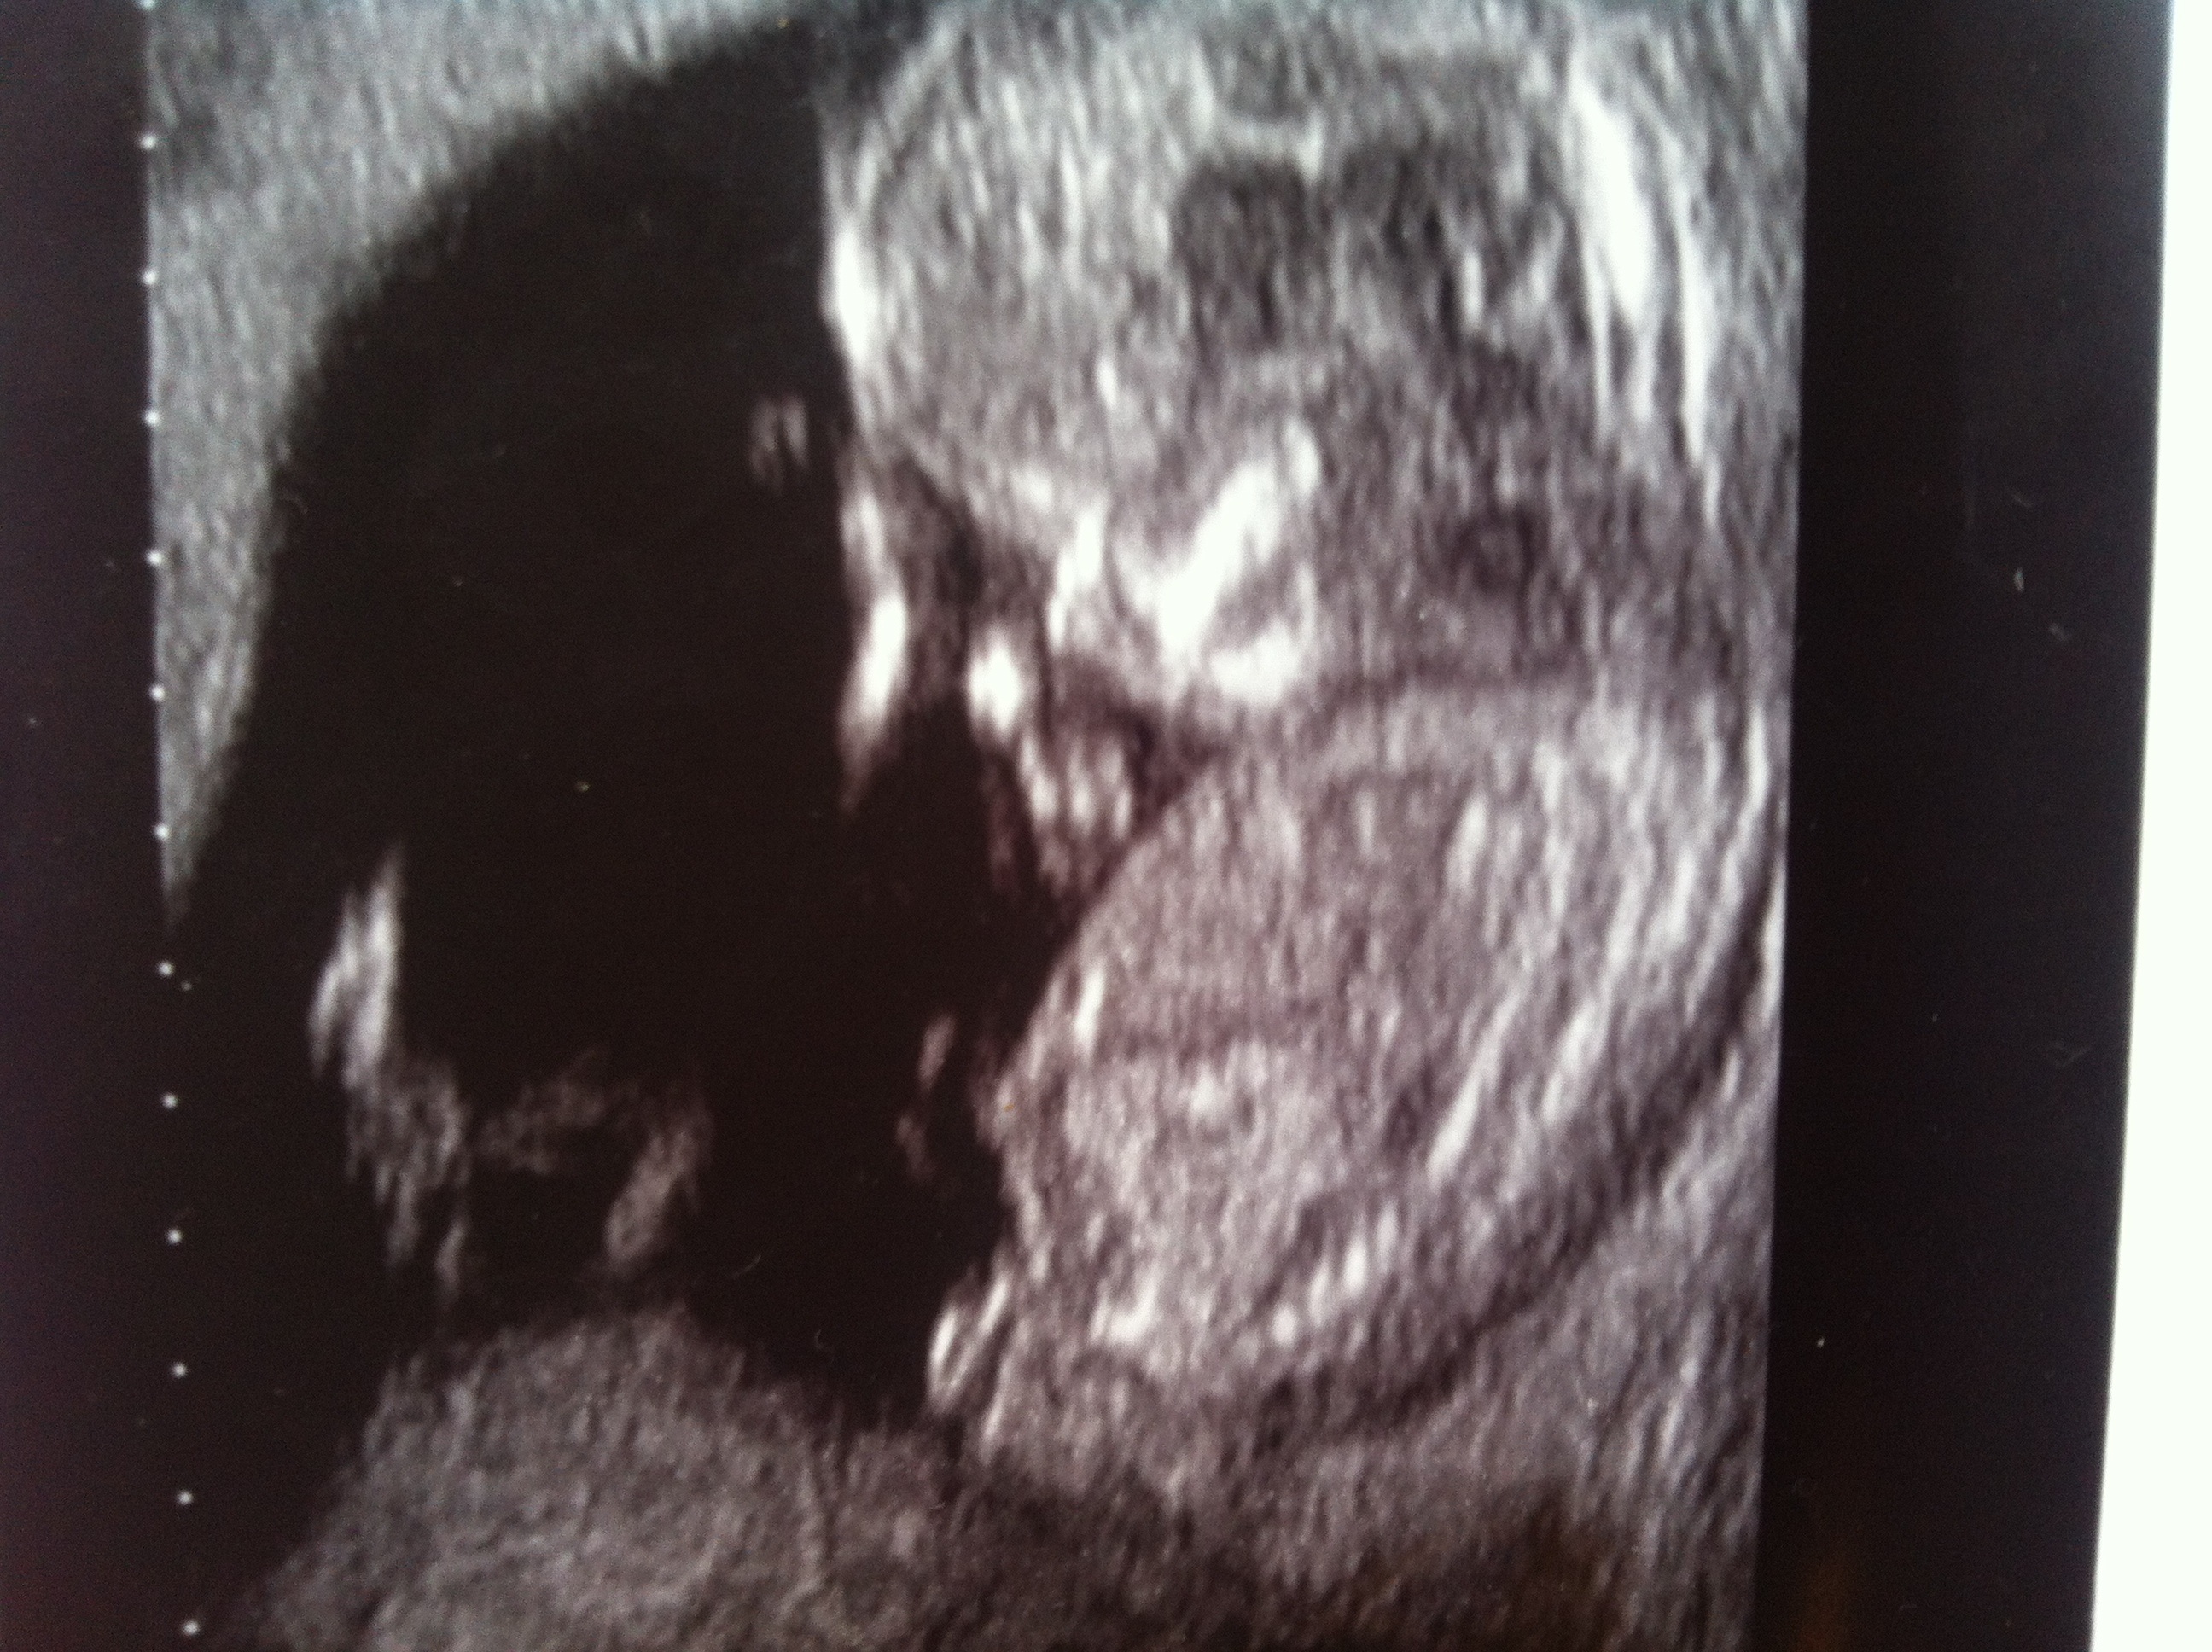

This pic might have a nub in it???

Or might not, I'm no good at this lol but let me know thanks x